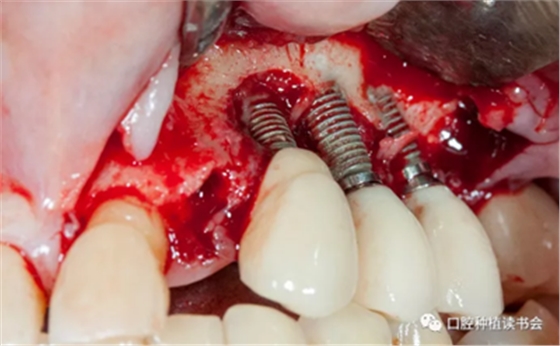

首先去除了螺絲固位的牙冠,引流膿液,翻全厚瓣暴露受感染部位的種植體。對暴露種植體進行種植體成形術,金剛砂車針磨除種植體表面凹槽(圖 20)。

圖20 種植體周圍有膿液滲出,翻瓣后行種植體成形術